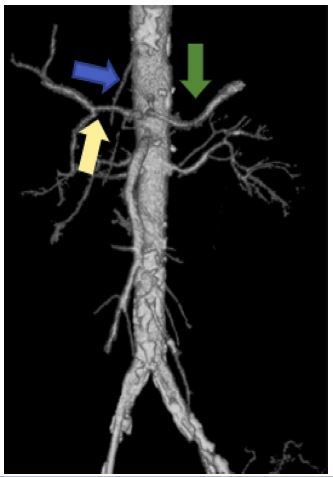

E.g., MALS i.e., Median arcuate ligament syndrome (Dunbar syndrome). The median arcuate ligament is a fibrous arch uniting the diaphragmatic crura at the level of the aortic hiatus and passes superior to the coeliac artery origin. However, if the insertion is low, it can cause abdominal pain. The diagnosis of coeliac axis compression / median arcuate ligament syndrome / Dunbar syndrome is done with conventional angiography/ CT angiography. The CECT imaging findings are characteristic focal narrowing in the proximal coeliac axis with a characteristic juxta-ostial hooked appearance with coeliac artery origin stenosis (Figure 7)[2].

Figure 7: Sagittal CT reformats showing juxta ostial fishhook configuration of the coeliac artery with narrowing of the coeliac artery near the origin (Red arrow).